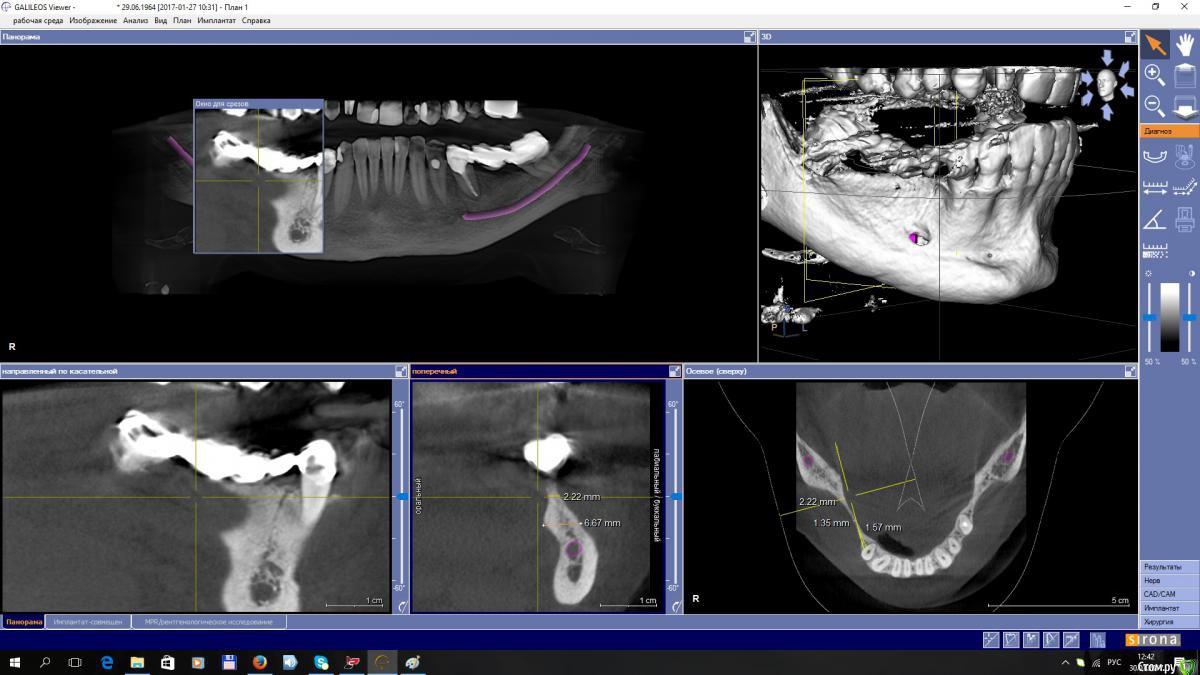

EEcho Опубликовано 30 января, 2017 Автор Поделиться Опубликовано 30 января, 2017 покажите срезы дальше(дистальнее) может целесообразно провести аугментацию дистально, возможно там ситуация получше... и сделать медиальную консоль на 5ый зуб.Срезы в области 45, 46, 47,48, Ссылка на комментарий

kamranchick Опубликовано 28 января, 2017 Поделиться Опубликовано 28 января, 2017 Уважаемые коллеги!Прошу совета!? Как увеличить объём, каким методом? Я в затруднении. За ранее большое спасибо!покажите срезы дальше(дистальнее) может целесообразно провести аугментацию дистально, возможно там ситуация получше... и сделать медиальную консоль на 5ый зуб. 1 Ссылка на комментарий

EEcho Опубликовано 30 января, 2017 Автор Поделиться Опубликовано 30 января, 2017 А какими методиками владеете?Наверное всеми ныне существующими. костной пластикой занимаюсь порядка 8-ми лет, но с таким ножевидным гребнем встречаюсь в первые. сплошная кортикалка, кровоснабжение гребня желает быть лучше, есть мысль разрез сделать на 3 мм ниже гребня язычно, без отслойки лоскута с язычной, и мембрану бить в открывшуюся кость. но есть сомнения. не могу прогнозировать отдаленный результат. Ссылка на комментарий